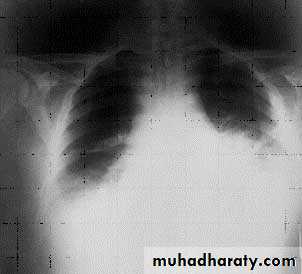

Infection causes septicaemia and death; pulmonary anthrax

(woolsorters’ disease) is a life-threatening pneumonia causedby inhalation of spores.

Pulmonary anthrax